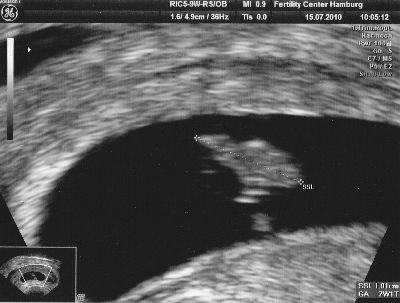

Das Herzchen hat weiterhin schön gebubbert und das Kleine schaut schon aus wie ein Gummibär - man konnte ganz klar die Arm- und Beinknospen erkennen!

Leider ist das Bild von heute aber aus einer anderen Perspektive... Rechnerisch bin ich einen Tag weiter als es auf dem Bild steht - aber ein Tag hin oder her ist doch wirklich wurscht... *gg*

Man hat nicht direkt die Ärmchen und Beinchen gesehen, sondern die Knospen - halt wie bei einem Gummibärchen so kleine "Gnubbel", aus denen Ärmchen und Beinchen werden... *gg*